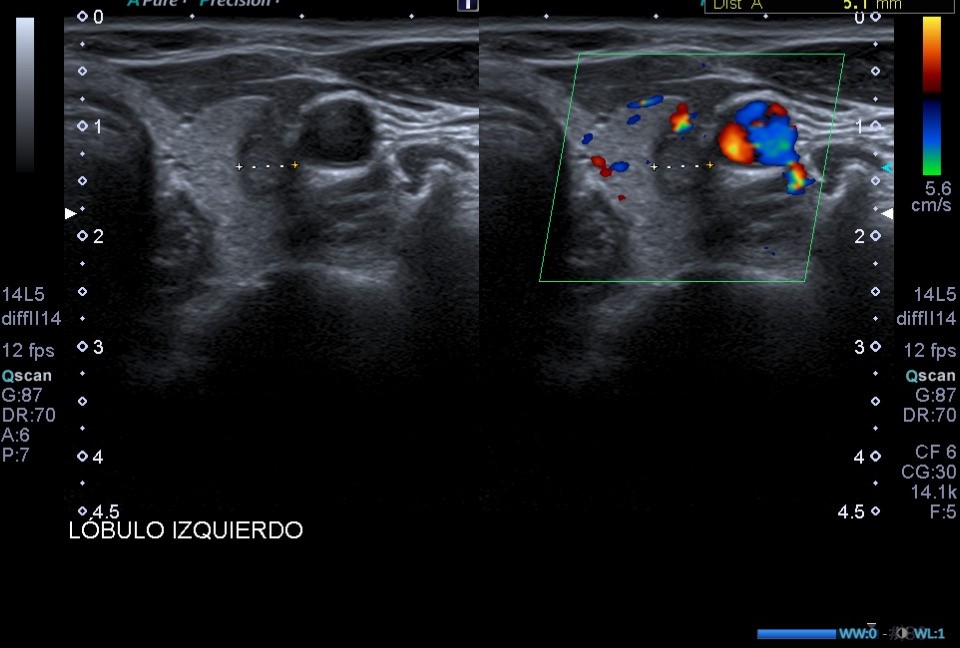

Ecografía de tiroides en consulta: En el LTI presenta dos lesiones nodulares en el área central del lóbulo tiroideo, presentando ambas un aspecto heterogéneo, bordes y márgenes mal definidos y microcalcificaciones.

Dada la presencia de nódulos tiroides con patrones ecográficos de alta sospecha de malignidad (bordes y márgenes mal definidos y presencia de microcalcificaciones), se solicita ecografía tiroidea reglada, y derivar a especialista en función de resultados.